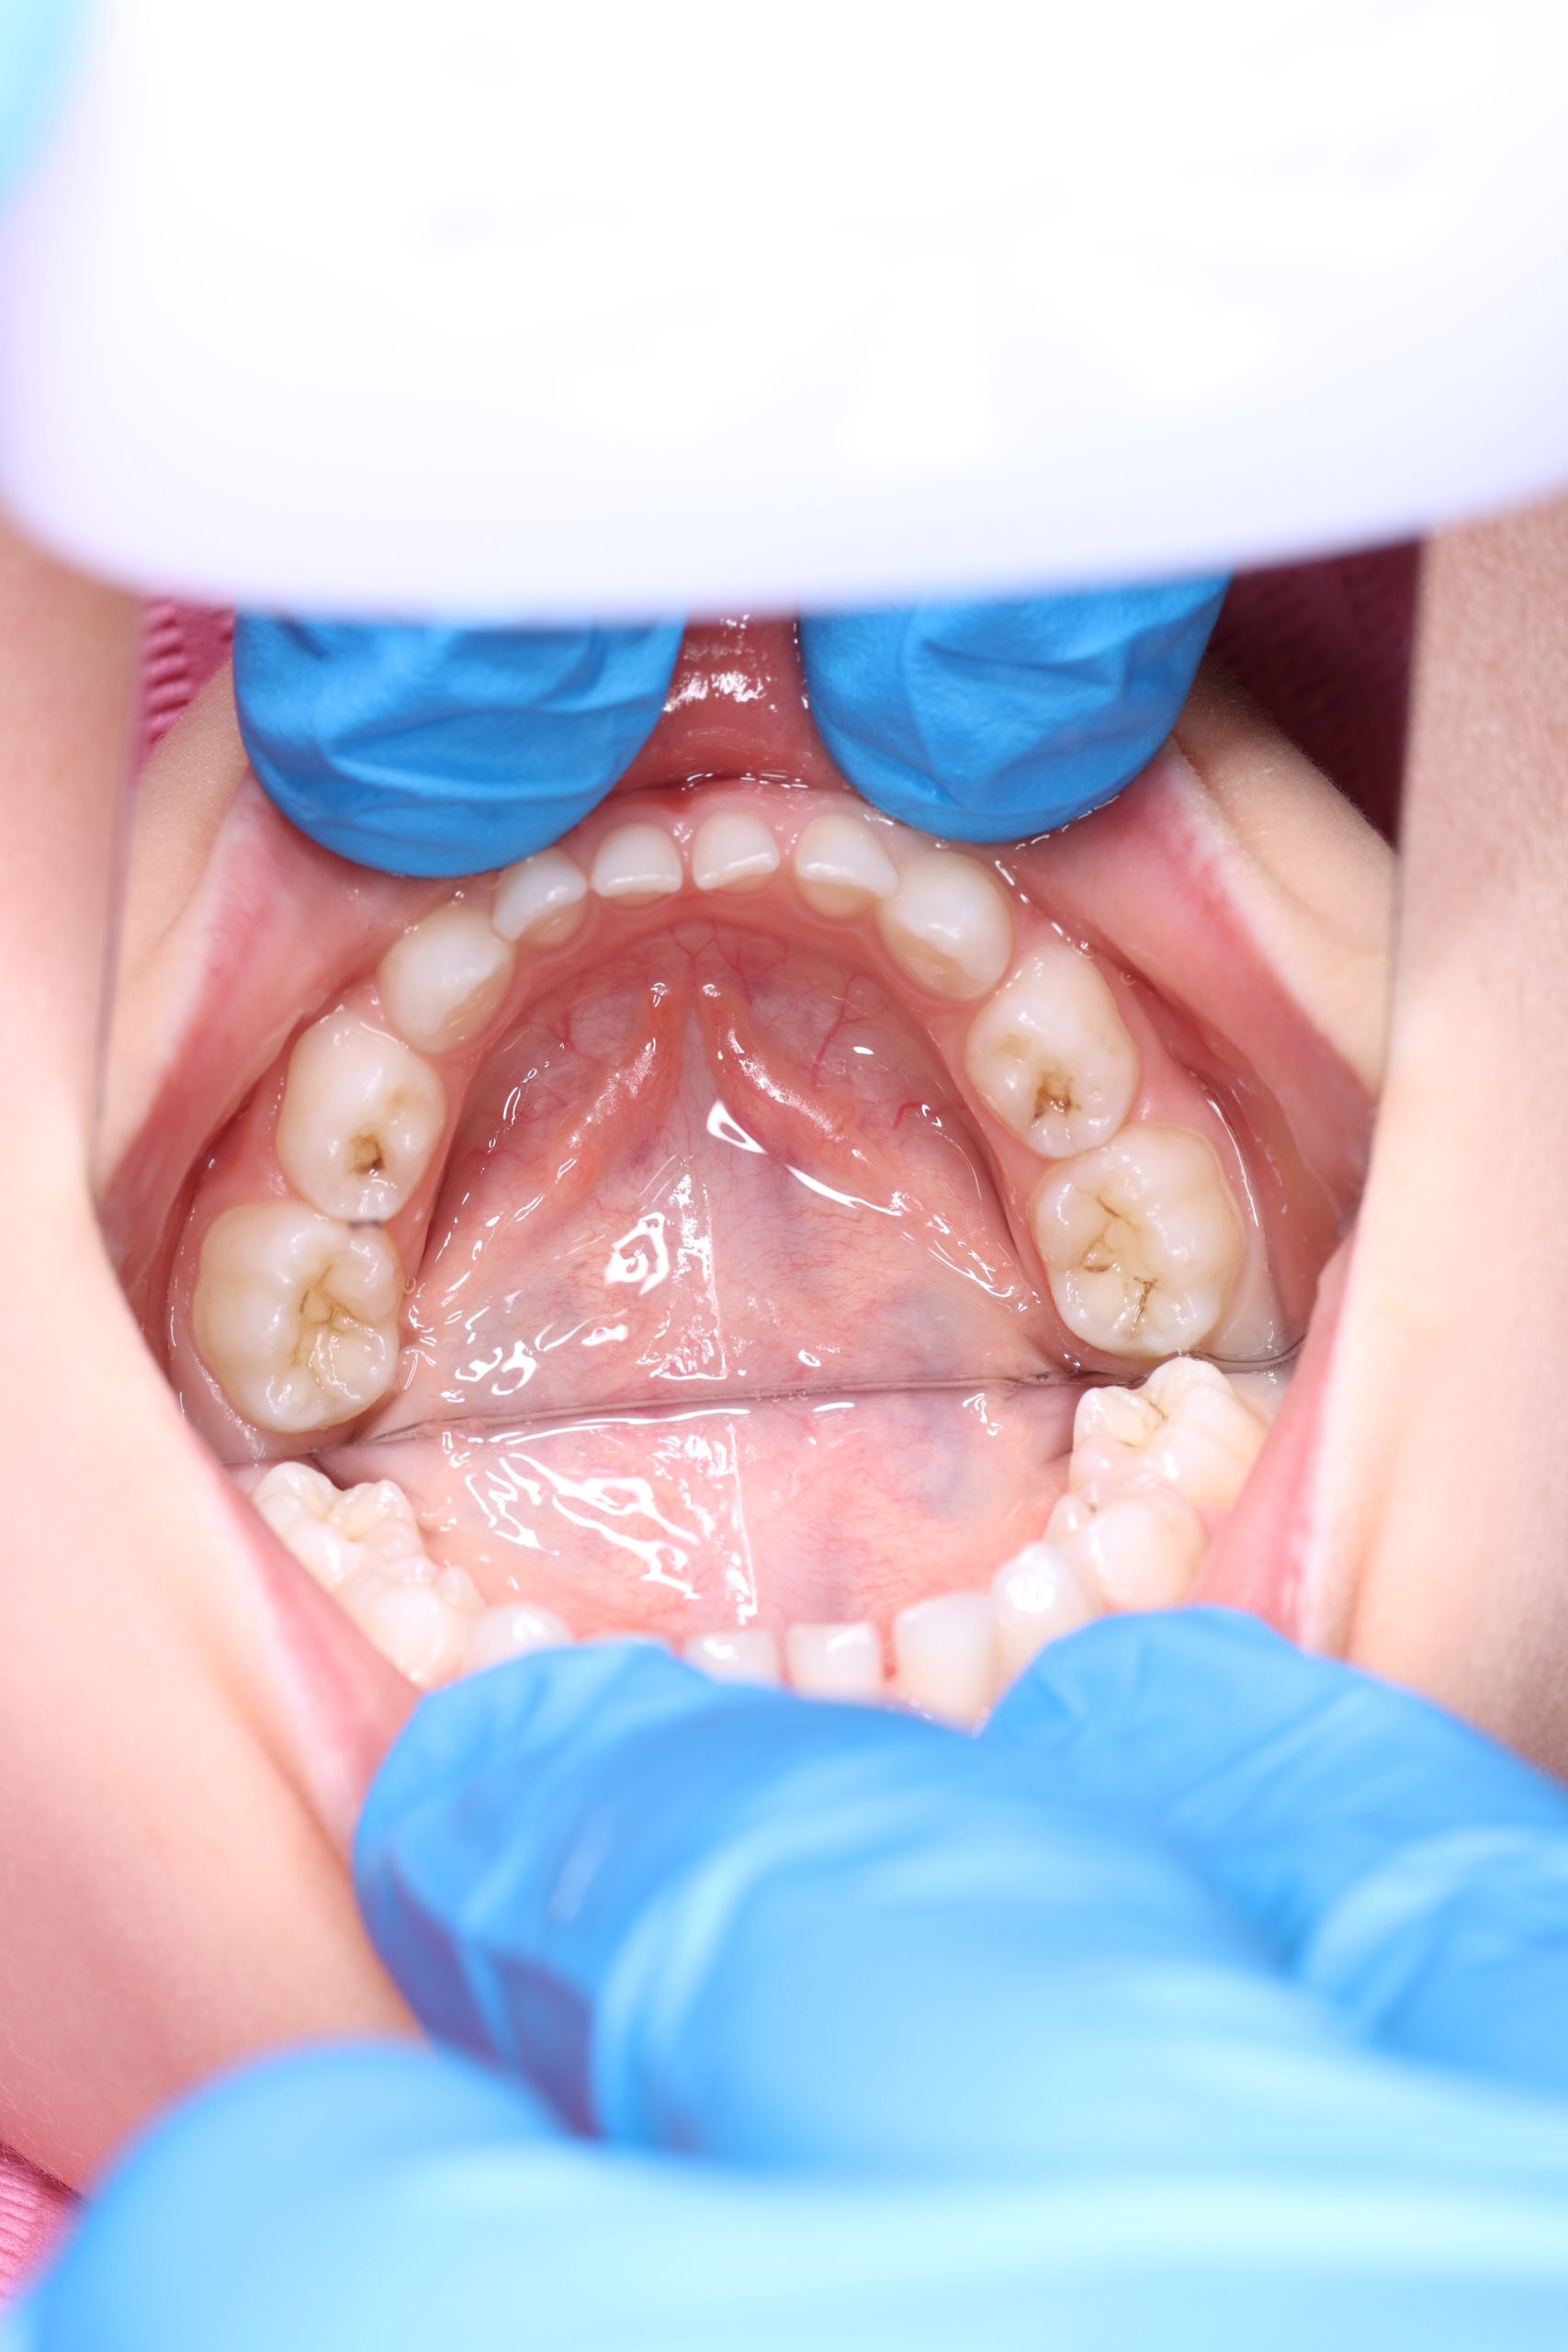

- Detailed Examination

We examine the condition of teeth, gums, and bite. - Plaque Disclosure with Special Indicators

Areas that weren’t cleaned well appear purple. The darker the shade, the older the plaque. This helps both kids and parents understand where brushing needs to improve. - Brushing Training & Home Care Tools Selection

Together with your child, we practice brushing techniques, correct mistakes, and provide personalized recommendations. We advise whether to use manual or electric brushes, floss, interdental brushes, or remineralizing gels. - Plaque Removal with AIRFLOW Prophylaxis Master (EMS, Switzerland)

From age 4–5 and up, we perform full GBT cleaning using an ultra-fine erythritol powder to clean even hard-to-reach areas gently and safely. It does not damage enamel and is ideal even around braces — no need to remove brackets or wires. - Tartar Removal (If Needed)